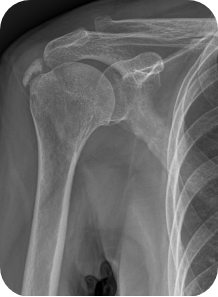

회전근개 질환, 오십견, 어깨 탈구 등 어깨 질환은 어깨의 통증과 고통을 야기합니다. 어깨 관절내시경 수술은 관절 질환이 의심되는 부위를 1cm 미만으로 최소절개한 뒤, 내시경 카메라와 수술 기구를 관절 내부에 삽입해 질환을 진단하고 치료하는 수술입니다. 화면을 통해 병변 부위를 직접 확인할 수 있어 손상 정도에 따라 파열된 힘줄을 봉합하거나 염증을 제거할 수 있습니다. CT나 MRI 등의 진단으로 잘 보이지 않던 곳까지 내시경을 삽입할 수 있어 적용 범위가 점점 넓어지고 있는 추세입니다.

- 회전근개 질환이 있는 경우

- 오십견, 어깨충돌증후군이 있는 경우

- 어깨탈구가 습관성으로 일어날 경우